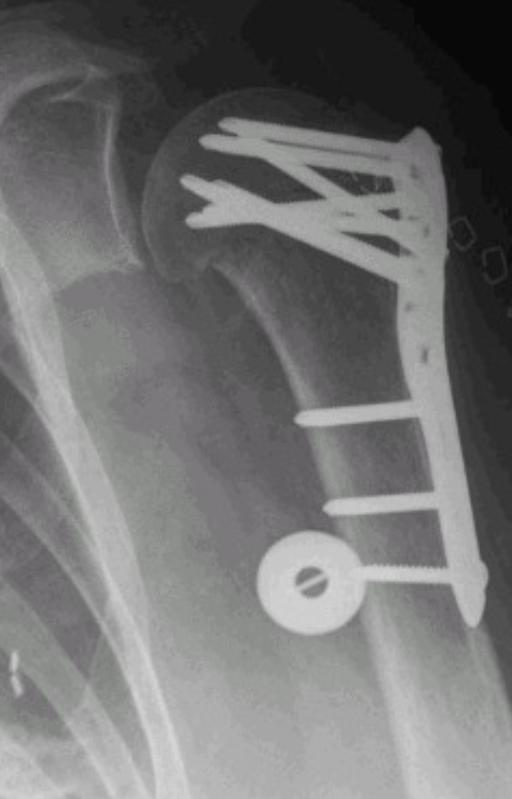

During placement of a proximal humerus locking plate, placement of an inferomedial calcar screw(s) can prevent what post-operative complication, especially in osteoporotic bone?

varus collapse